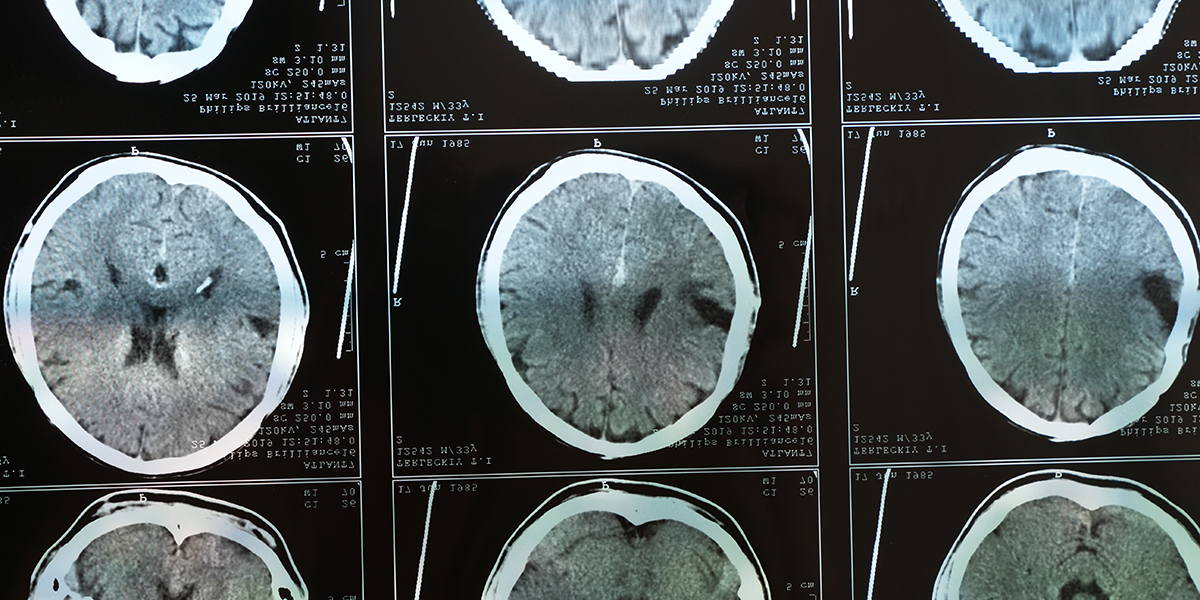

Male patient with previous motorcycle accident displayed leftward midline shift and brain abnormalities on scan.